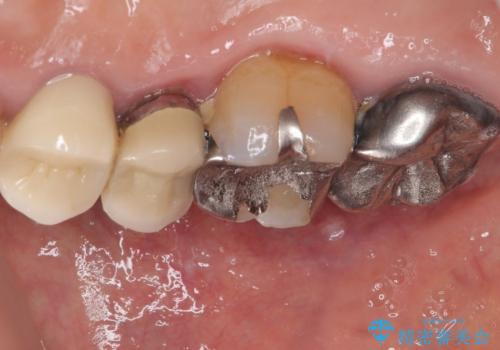

残存歯質の確認と感染リスクのチェック

ファイバーコアを築造・精密な支台歯形成と印象採得